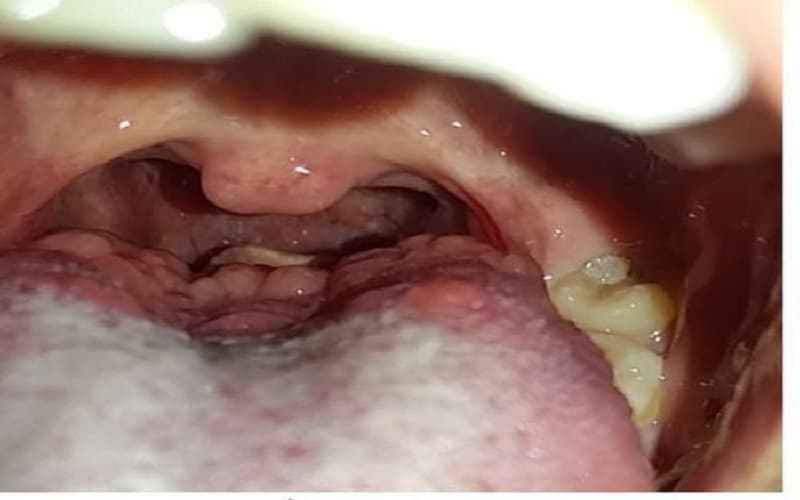

Hình ảnh tổn thương khi quan sát:

- Tăng sinh lympho: Thường là nhiều nốt nhỏ, phân bố hai bên, khá đối xứng, màu hồng hoặc hồng thẫm.

- U ác tính: Thường là một khối đơn độc, hay xuất hiện một bên, bề mặt sần sùi và dễ loét chảy máu, Kích thước tăng dần theo thời gian